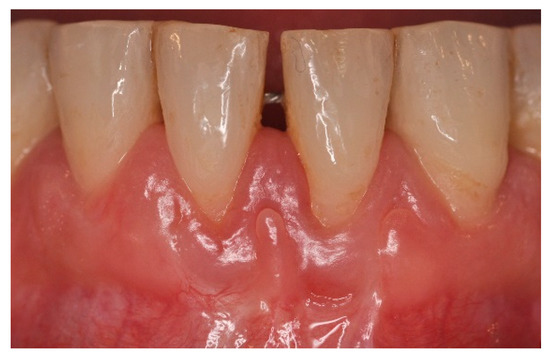

6. Results